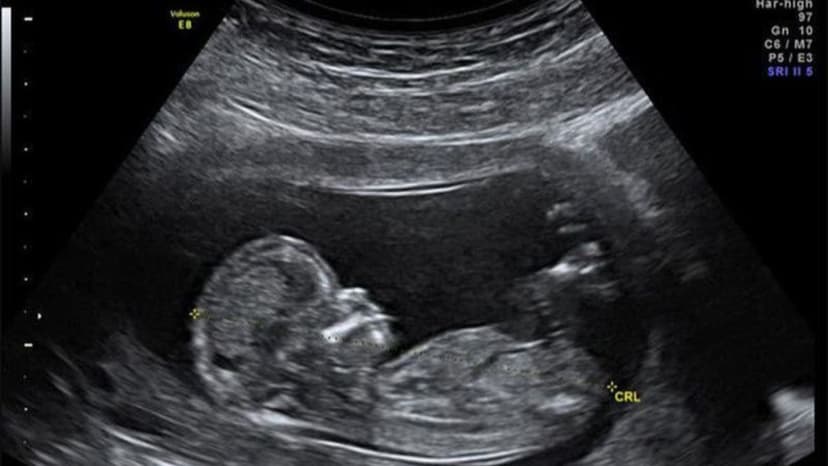

Trong cơ thể người, xương đùi là phần xương có chiều dài lớn nhất. Việc đo đạc kích thước xương đùi trong các buổi siêu âm giúp ước tính tuổi thai và đánh giá sự phát triển toàn diện.

Dựa vào các dữ liệu y khoa thống kê, kích thước xương đùi luôn có sự biến đổi nhỏ tùy thuộc vào từng bào thai khác nhau. Ở mốc siêu âm tuần thứ 33, kết quả đo đạc thường ghi nhận các thông số tiêu chuẩn như sau:

- Giá trị trung bình của chiều dài xương đùi thường đạt mức 63mm.

- Ngưỡng giới hạn an toàn cho phép của chỉ số này sẽ dao động từ 58mm đến 70mm.

- Một số tài liệu chuyên ngành sản khoa cũng nhận định chiều dài xương đùi giai đoạn này nằm trong khoảng 57mm đến 68mm.

Sự chênh lệch nhẹ giữa các bảng tiêu chuẩn là hiện tượng bình thường. Bác sĩ sẽ so sánh kết quả siêu âm cụ thể của từng bé với biểu đồ tăng trưởng để đưa ra đánh giá chính xác nhất.